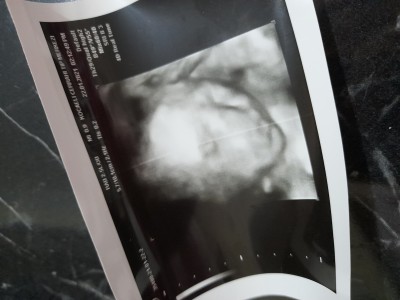

image

29.haftadayım şuan bu resmi özel hastane verdi devletede gittim 1 kere onda hiç bebek bile gözükmüyordu saçma bi fotoğraf verdi